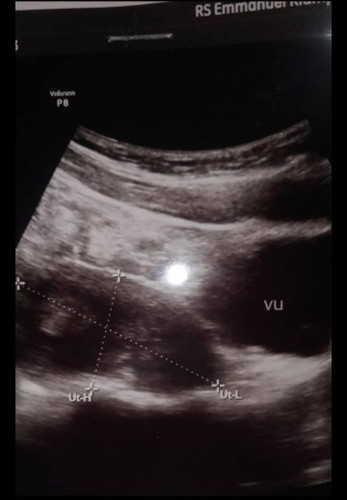

Bunda" disini tau ga kira" ini udah brp week ya

Hasil usg

Dibawah hasil usg itu ada keterangan nya bun tinggal baca aja, dokter nya bilang apa? Itu kantung hamil, janin atau kista?